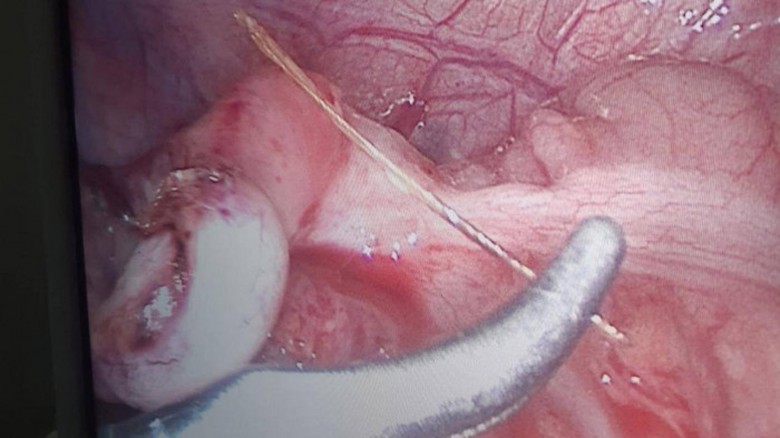

Trong quá trình phẫu thuật, kíp mổ do Thạc sĩ - bác sĩ Lê Văn Khen, Trưởng khoa Ngoại của bệnh viện phát hiện nguyên nhân viêm ruột thừa là do dị vật là một đoạn xương cá dài khoảng 2cm xuyên thủng ruột thừa.

Sau khi lấy dị vật ra, các bác sĩ mới tiến hành cắt ruột thừa cho bệnh nhân.